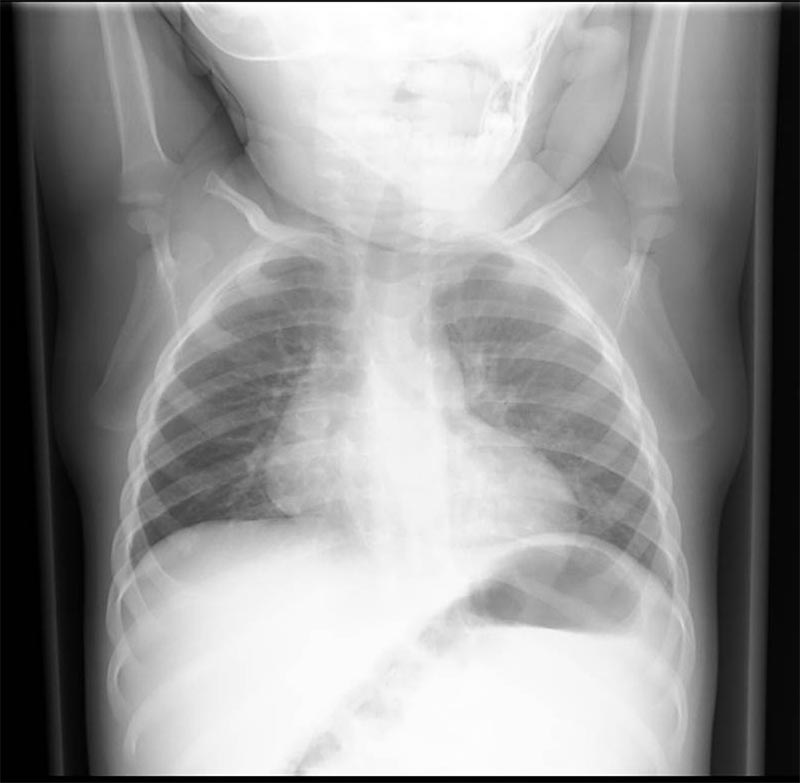

10-month-old male infant presents to the ED by EMS with vomiting and altered mental status (AMS). Infant arrives to the ED awake but poorly interactive. Ultimately, the infant will be diagnosed with intussusception and hypovolemic shock based on the history, physical exam and ultrasound findings. Learners are expected to establish a differential diagnosis of AMS appropriate for an infant, demonstrate appropriate resuscitative interventions, and use appropriate imaging and labs to help identify the cause of AMS.